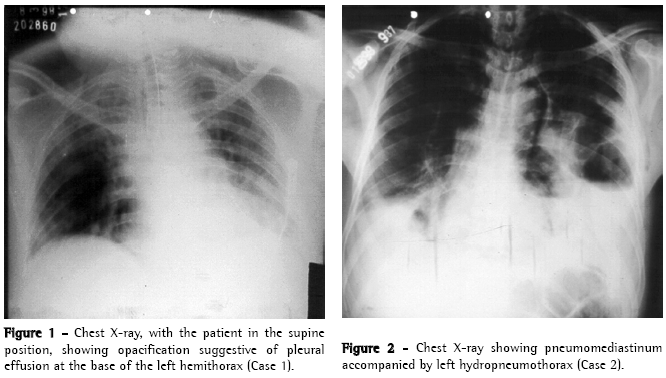

A 49-year-old male patient was admitted to the Emergency Room of the Walfredo Gurgel Hospital for surgical repair of a complicated umbilical hernia with intestinal obstruction. Approximately 10 h after the surgical repair, the patient presented intense chest pain, diaphoresis, hypotension and dyspnea, which was initially treated as acute myocardial infarction. A chest X-ray (Figure 1) revealed left pleural effusion, leading to the initial hypothesis of pulmonary embolism. A thoracocentesis revealed an accumulation of dark fluid, suggestive of gastric stasis in the left pleural cavity. During the directed interview, the patient revealed that he had vomited excessively during the entire hospital stay. An esophagoscopy revealed extensive impairment of the distal esophageal lumen, which was exuding a large quantity of secretion similar to that obtained in the thoracocentesis, obstructing proper visualization of the defect.

A 38-year-old male patient was admitted to the Emergency Room of the Walfredo Gurgel Hospital presenting spontaneous subcutaneous emphysema. During the directed interview, the patient reported alcoholism and recent episodes of vomiting after eating. He had no complaints of intense chest pain, indisposition or respiratory discomfort during the initial assessment. The physical examination and chest X-ray revealed pronounced subcutaneous emphysema in the chest and neck and condensation suggestive of pleural effusion in the left lung base (Figure 2). Fluid drawn during the thoracocentesis was dark in color with an aspect suggestive of gastric contents, leading to the suspicion of esophageal rupture, which was confirmed by the esophagogram.